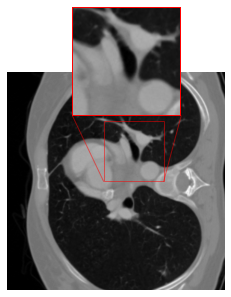

However, our application of this strategy in CT results in artifacts (cf. Figure 1(c)) at the patch boundaries, showcasing a sudden shift from intense to subtle smoothing with the cropping strategy. A reason for this might be that the errors are typically not Gaussian white noise, but more involved. For mitigating the artifacts, we modify the cropping approach of [47] by implementing padding in the output of the FBP to align with the network architecture. The DRUNet architecture operates solely on images sized as multiples of due to its four downsampling steps, whereas the LoDoPaB-CT dataset comprises images of size , which does not conform to this requirement. To address this, we apply mirror padding to enlarge the images to before passing them through the network and subsequently cropping them back to the original size of Figure 2 illustrates the suitability of the proposed strategy. (We point out that the image depicted in Figure 2 represents one of the most challenging reconstructions within the dataset.)

Effectiveness of the Rotational Augmentation

To evaluate the impact of rotational augmentation, we conducted an experiment by training two networks: one with rotational augmentation and the other without. The objective was to investigate the network’s response to input images under different orientations. Specifically, we applied two scenarios: firstly, inputting images as they are, and secondly, rotating them by 90° before feeding them into the networks. Results depicted in Fig. 3 illustrate a noteworthy observation. For the network with rotational augmentation during training (cf. 2(e) and 2(f)), the output remains consistent regardless of the input image’s orientation. However, for the network trained without rotational augmentation (cf. 2(c) and 2(d)), the output varies between the normal and rotated input scenarios. This experiment highlights the effectiveness of rotational augmentation in achieving network equivariance and ensuring consistent performance across different orientations of input images.